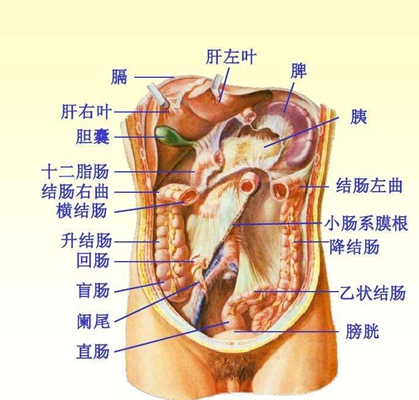

盲腸的位置 (50)

盲腸的位置 (6)

盲腸的位置 (7)

盲腸的位置 (8)

盲腸的位置 (9)

盲腸的位置 (46)

盲腸的位置 (47)

盲腸的位置 (48)

盲腸的位置 (49)

盲腸的位置 (5)

盲腸的位置 (42)

盲腸的位置 (43)

盲腸的位置 (44)

盲腸的位置 (45)

盲腸的位置 (41)

盲腸的位置 (40)

盲腸的位置 (30)

盲腸的位置 (31)

盲腸的位置 (32)

盲腸的位置 (33)